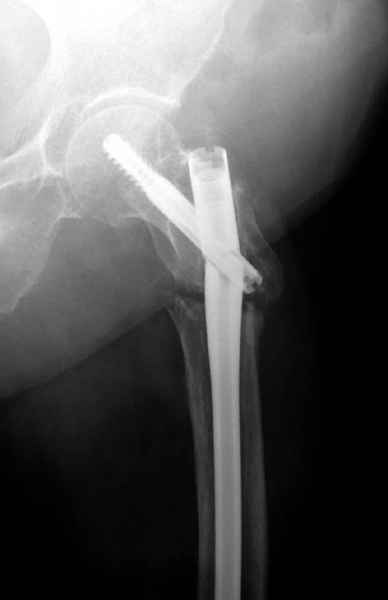

77 летняя больная направлена в нашу клинику на дальнейшее лечение. Из истории, травму получила в сентябре 2007 года и по поводу перелома шейки бедра больная была проперирована тремя каннюлированными шурупами с явным нарушением технологии установки шурупов. Внизу вместо одного шурупа имеется два, что привело к стрессу латерального кортекса. Через месяц по поводу ятрогенного подвертельного перелома сделана фиксация длинной Гамма 3. Установлен без проксимальной блокировки? (set screw). В данный момент имеется несостоятельность конструкции и ложный сустав. Передвигается с помошью костылей, конечность укорочена на 2 см. Какие будут рекомендации?Djoldas Kuldjanov, MDDepartment of Orthopedic SurgerySt. Louis University Medical Center

Михаил, здравствуйте. Если присмотреться - на четвертом снимке есть перелом гвоздя по отверстию.